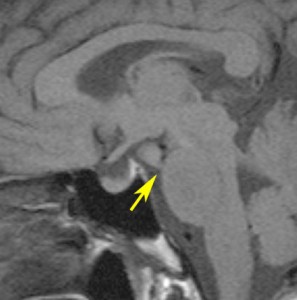

小さな典型的な視床下部過誤腫

無症候で発見されたpedunculated typeです。視床下部の底面からぶら下がるようにしてあります。左のCISS画像で形がよくわかります。中央のT1では灰白質と等信号です。右のT2では高信号となっています。

乳頭体(矢印)からは離れているタイプです。ですから笑い発作を生じません。右側のガドリニウム増強画像ではまったく増強されていないのが特徴です。